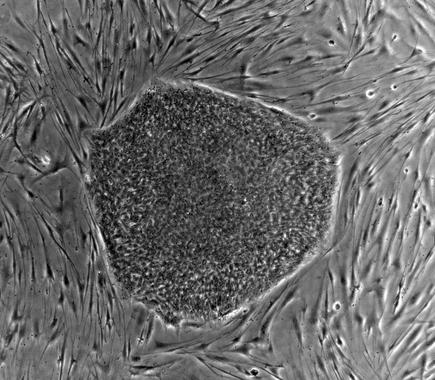

Ahora, investigadores de todo el mundo reunidos en el proyecto Grandiose han explorado paso a paso los caminos de la reprogramación y han descubierto un nuevo tipo celular resultante del proceso: las células de clase F, llamadas así por el adjetivo fuzzy (borroso, en inglés), por la apariencia de las colonias que forman. Estas células son estables, lo que podría facilitar su uso terapéutico. Además, los nuevos detalles observados en el estudio permitirán controlar mejor el proceso. Los resultados se publican en una serie de cinco artículos en las revistas Nature y Nature Communications.

Dos de los artículos revelan detalles del proceso de reprogramación que determinan los tipos de células que se obtienen de ella. Gracias a ese examen exhaustivo, los investigadores han identificado las células de clase F como un tipo diferente a las ya conocidas.

Las F proliferan a gran velocidad y son estables, lo que, en principio, podría ser útil para producir células a gran escala, un requisito necesario en las futuras terapias regenerativas para combatir enfermedades, como la diabetes. Su capacidad de reproducción “es positiva, pero la aplicación clínica todavía no es segura, porque las mutaciones derivadas de la inserción podrían formar tumores”, explica Izpisua Belmonte.